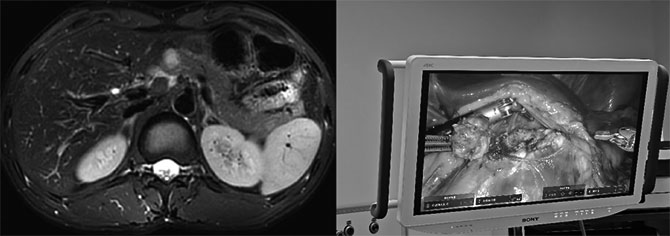

37岁的吴先生(化名)在体检中发现了胰腺颈部占位,为了寻求更好的治疗,家属陪同他到广东省人民医院胰腺中心就诊。陈汝福教授随即组织科室团队进行详细的病情讨论与手术方案制定。考虑到病人年轻,且瘤体位置靠近胰管及动脉,为了尽量减少术中出血量,减少麻醉时间,为患者保留更多正常胰腺,决定采用医院刚刚引入的国产手术机器人为吴先生实施胰腺保留功能手术。

当日,手术室和麻醉团队通力配合,一切准备工作就绪,陈汝福教授主刀为患者实施机器人辅助胰腺肿瘤局部剜除术。术中,凭借机器人精细清晰的视野,陈汝福教授打开大网膜,暴露胰腺前方。可见肿瘤位于胰腺颈部前方,与周围系膜有明显粘连,肿瘤右后侧与下缘可见多个小动脉残端,利用机器人双极止血。继续提起肿瘤,靠近肿瘤底部、肿瘤与胰管附近处,钝性分离根部并完整切除肿瘤。检查创面,仔细缝合血管残端,明确止血。随后操控机器人分离、止血、缝合动作丝滑,仅仅上机10分钟,便将胰腺肿瘤完整地切除下来,并且完美保留了消化道的生理结构及胰腺生理功能,整台手术出血不到5ml。